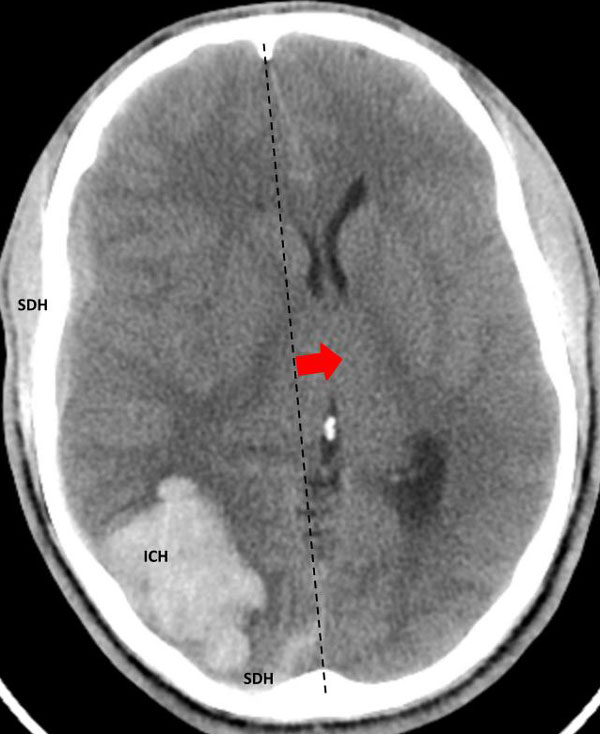

The patient was taken to the angio-suite where an angiogram confirmed a high flow, high pressure AVM fed primarily by the posterior cerebral artery with a small collateral from the middle cerebral artery (Fig 2 and 3). The AVM drained into a tortuous, partially occluded and stenotic single draining vein.

Fig 2. AP view, mid-arterial phase of a right internal carotid artery (ICA) injection. The large tortuous draining vein (yellow star) with the suggestion of clot (dotted circle) can be seen. AVM nidus (red arrow), MCA (middle cerebral artery, ACA (anterior cerebral artery).